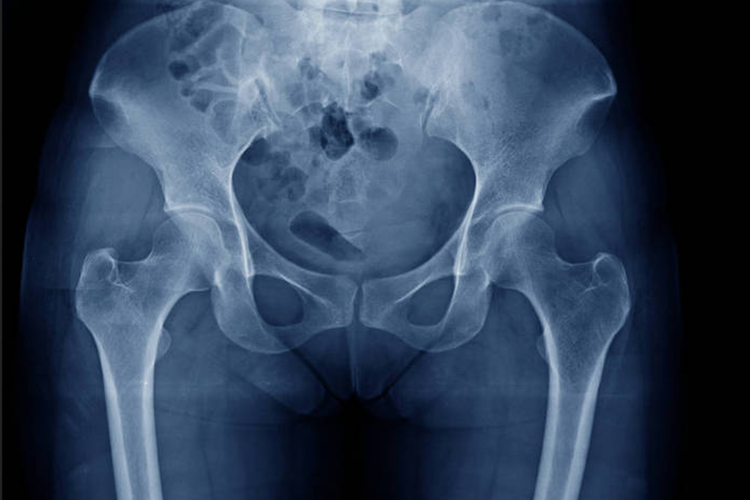

正常髋关节X光片可见骨盆居正,双侧髋臼内股骨头外形光滑,间隙正常,是人体负重、直立和运动的重要功能构架。

正常髋关节X光片下可见髋关节由髋臼和股骨头组成,髋臼对股骨头的覆盖面积达到70%-80%,股骨头与髋臼有1-2mm的透亮间隙,双侧髋臼内股骨头外形光滑,可见边缘光滑整齐的线样致密影。